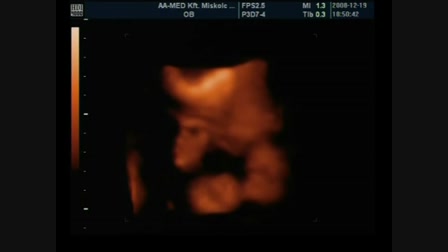

pappákos: Ákos saját éneke